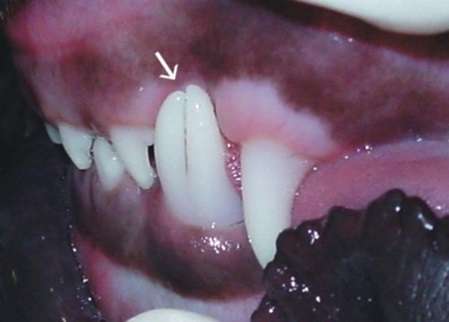

Zwillingszahn aus einem Zahnkeim

(aus: Developmental Structural Tooth Defects in Dogs - Experience From Veterinary Dental Referral Practice and Review of the Literature. Boy S, Crossley D, Steenkamp G. Front Vet Sci. 2016 Feb 8;3:9. doi: 10.3389/fvets.2016.00009. eCollection 2016. Review.)